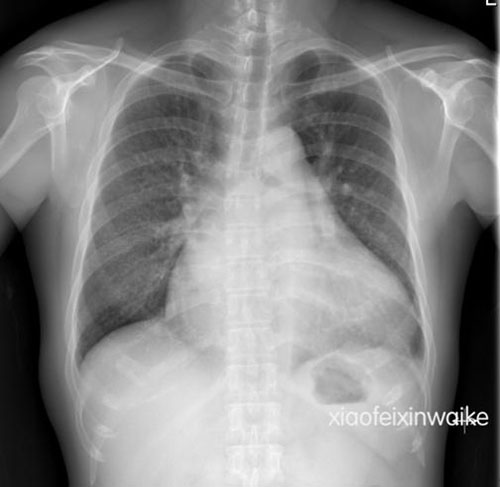

这是一名男性患者,49岁,因反复劳力性呼吸困难14年,加重伴双下肢浮肿1月余入院。心脏超声发现这是一颗早就不堪重负的心脏:风湿性心脏病,联合瓣膜病,主动脉瓣重度狭窄,收缩峰值压差高达94mmHg;二尖瓣重度狭窄,瓣口面积仅为正常人的1/4;三尖瓣返流面积达到了惊人的19.3 cm2;肺动脉收缩压高达119mmHg,更是正常上限的4倍。心胸比例为0.71(图1)。

图1. 患者术前的胸片